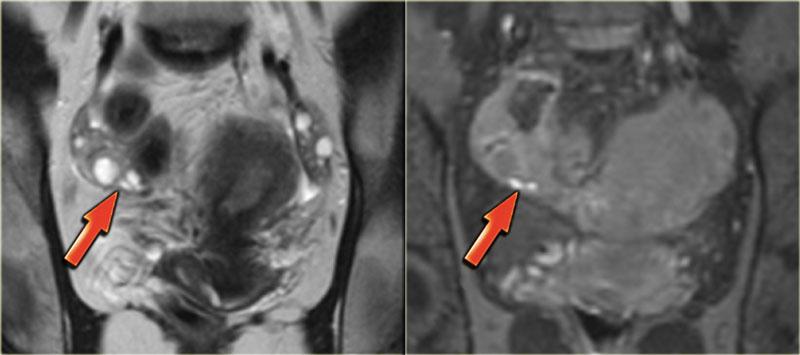

TRÁI: T2W mặt phẳng trán: buồng trứng áp sát nhau do dính. PHẢI: T1W+FS mặt phẳng trán minh họa các ổ xuất huyết nhỏ (mũi tên đỏ)

Hình ảnh T2W và T1W kỹ thuật ức chế mỡ bên trái cho thấy bệnh nhân lạc nội mạc tử cung có hai buồng trứng áp sát nhau (‘buồng trứng hôn nhau’), là kết quả của sự hình thành dính lan rộng.

Ở bệnh nhân này, một nang xuất huyết nhỏ của buồng trứng trái và một mảng nông xuất huyết cũng được ghi nhận (tăng tín hiệu trên T1, mũi tên đỏ).